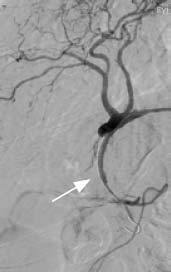

Эффективность рентгенэндоваскулярного лечения, заключающаяся в остановке продолжающегося желудочно-кишечного кровотечения и профилактике его рецидивов, составила 100%. Эффективность имплантации стентов-графтов подтверждена с помощью контрольной ангиографии. На рис. 2 и 3 представлены фотографии ангиограмм брюшного отдела аорты и ангиографические результаты имплантации стента-графта в желудочно-двенадцатиперстную артерию в области шейки ложной аневризмы.

Рис. 2. Ангиограмма брюшного отдела аорты. Стрелкой указана ложная аневризма желудочно-двенадцатиперстной артерии